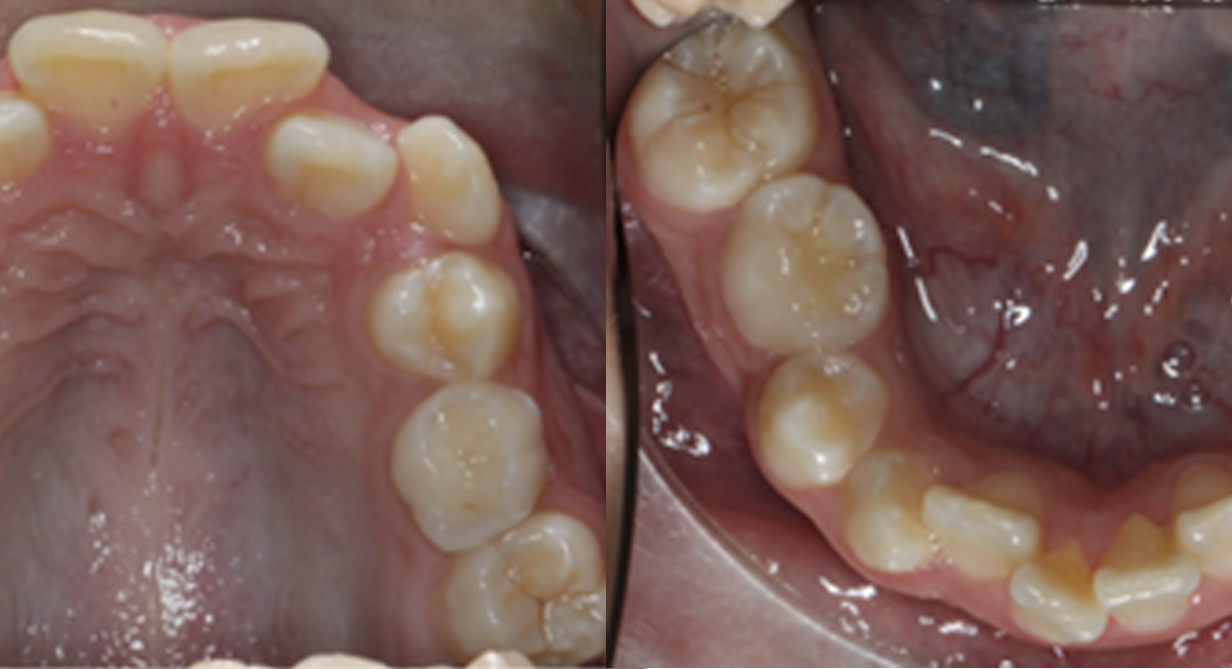

La combinación de estos distintos elementos hacen imposible determinar una edad en la que los pacientes deban acudir al ortodoncista, sin embargo, una premisa básica sería el cuidar que los dientes erupcionen en el centro del hueso alveolar.

Si se llegara a detectar cualquier tipo de malposición dentaria, sin importar el tipo de dentición, es preferible consultar con un ortodoncista, ya que se debe evitar a toda costa que los dientes erupcionen próximos o incluso fuera de las corticales; previniendo así defectos periodontales, inclusión de caninos y la vestibularización de dientes posteriores con la consecuente extrusión de cúspides palatinas y afectaciones en la articulación temporomandibular.